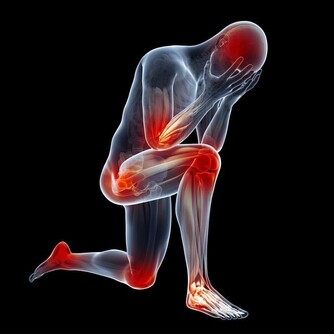

長期飲酒過量對身體有什麼危害?

① 肝臟受損。喝酒過度,容易使脂肪堆積在肝臟,損傷肝細胞,甚至誘發脂肪肝。

② 胃潰瘍。酗酒還會嚴重刺激胃部,容易造成胃出血,威脅生命安全。

③ 中樞神經受損。酒精還會使神經系統受到損壞,表現出記憶力下降、精神異常等現象。

④ 猝死。過量飲酒,還可能會抑制腦部呼吸中樞,導致呼吸停止;同時降低血糖,引起猝死。